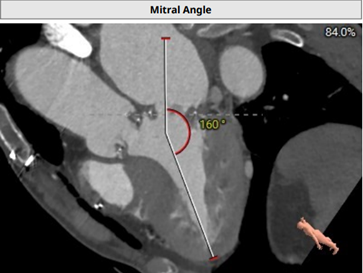

开口面积272.8mm²、瓣架高度12.6mm和入路角度160°: